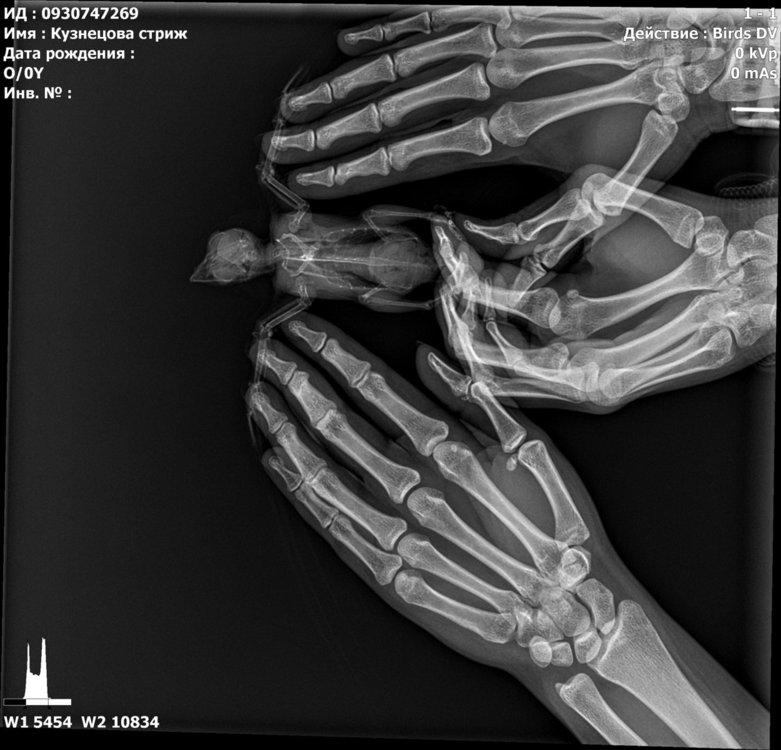

сделали ренген стрижу, только специалистов по птицам в клинике нет.. хотя бы знать нет ли  ничего серьезного.. ехать в москву нет возможности.

@валена простите, не видела раньше вашу тему. Что-то с оповещениями не то. К сожалению, по данному рентгену можно очень мало чего сказать. Он совершенно бездарен.

Разве что если переделать? Стрижа для снимка кладут на спинку и полностью  раскрывают его крылышки. Нужен только 1 снимок.